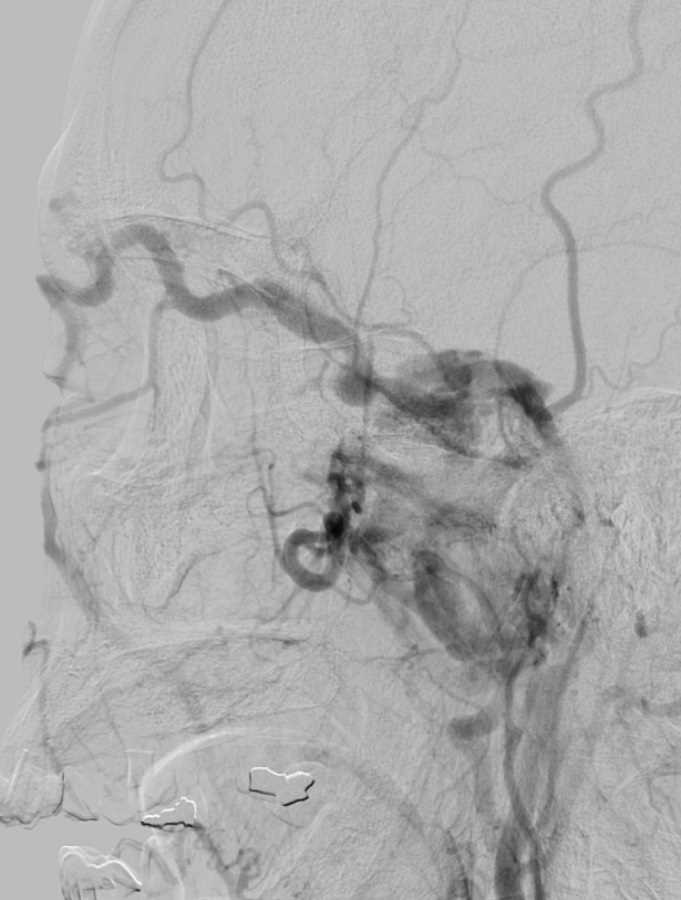

These images demonstrate a well-circumscribed submucosal hypodense cystic lesion in the right nasopharynx which is to the right of midline in a preadolescent child with prominent, but age-appropriate adenoids. Hounsfield unit interrogation shows that it is not simple fluid or soft tissue density. The differential considerations include a mucous retention cyst, Tornwaldt cyst, or adenoidal abscess. This patient was scanned for head trauma so infection is unlikely. Given that it was off midline the best diagnosis is retention cyst of the nasopharynx, likely in the lateral pharyngeal recess. If it was midline, the leading differential would be a Tornwaldt cyst (cyst of notochordal remnant).